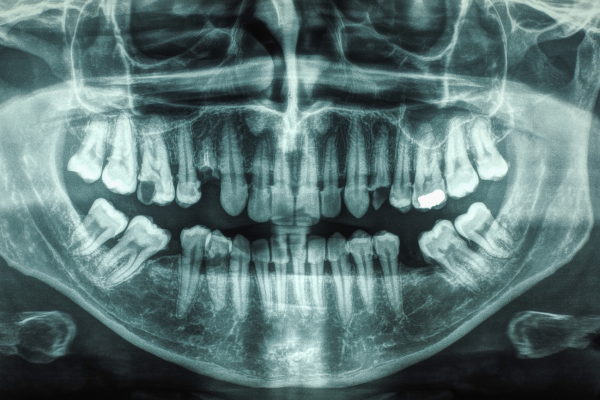

Dental X-ray of a human mouth

Panoramic – A panoramic view X-ray shows all the upper and lower teeth, large portions of the jaws and other structures in one large picture. It is often used to find unerupted teeth, cysts, fractures, retained root fragments, and other conditions of the jaw. It does not generally show enough detail to be useful for detection of decay and bone loss from periodontal disease.